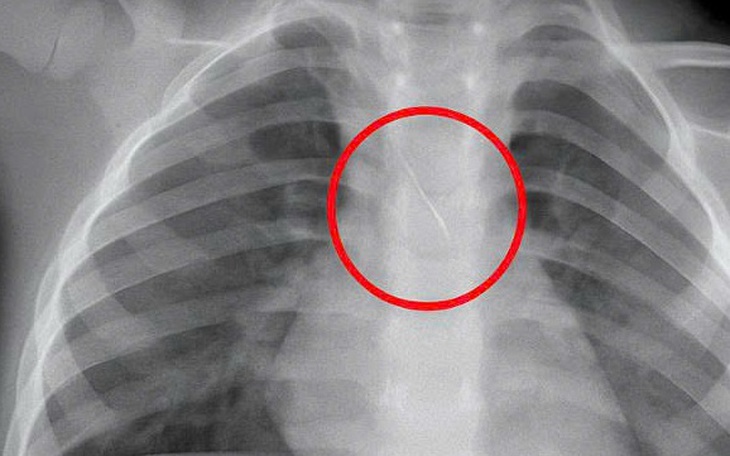

Bệnh viện Đà Nẵng cũng tiếp nhận bà L.T.T.R. (69 tuổi, Đà Nẵng) ho khan kéo dài hơn 3 tháng, kèm sốt, đau ngực và viêm phổi tái phát. Chụp X-quang và CT cho thấy tổn thương phổi kèm hình ảnh nghi dị vật trong phế quản. Khi nội soi, bác sĩ phát hiện một mảnh xương sắc kích thước khoảng 2 x 1,5cm nằm ở ngã ba phế quản thùy trên - thùy dưới trái.